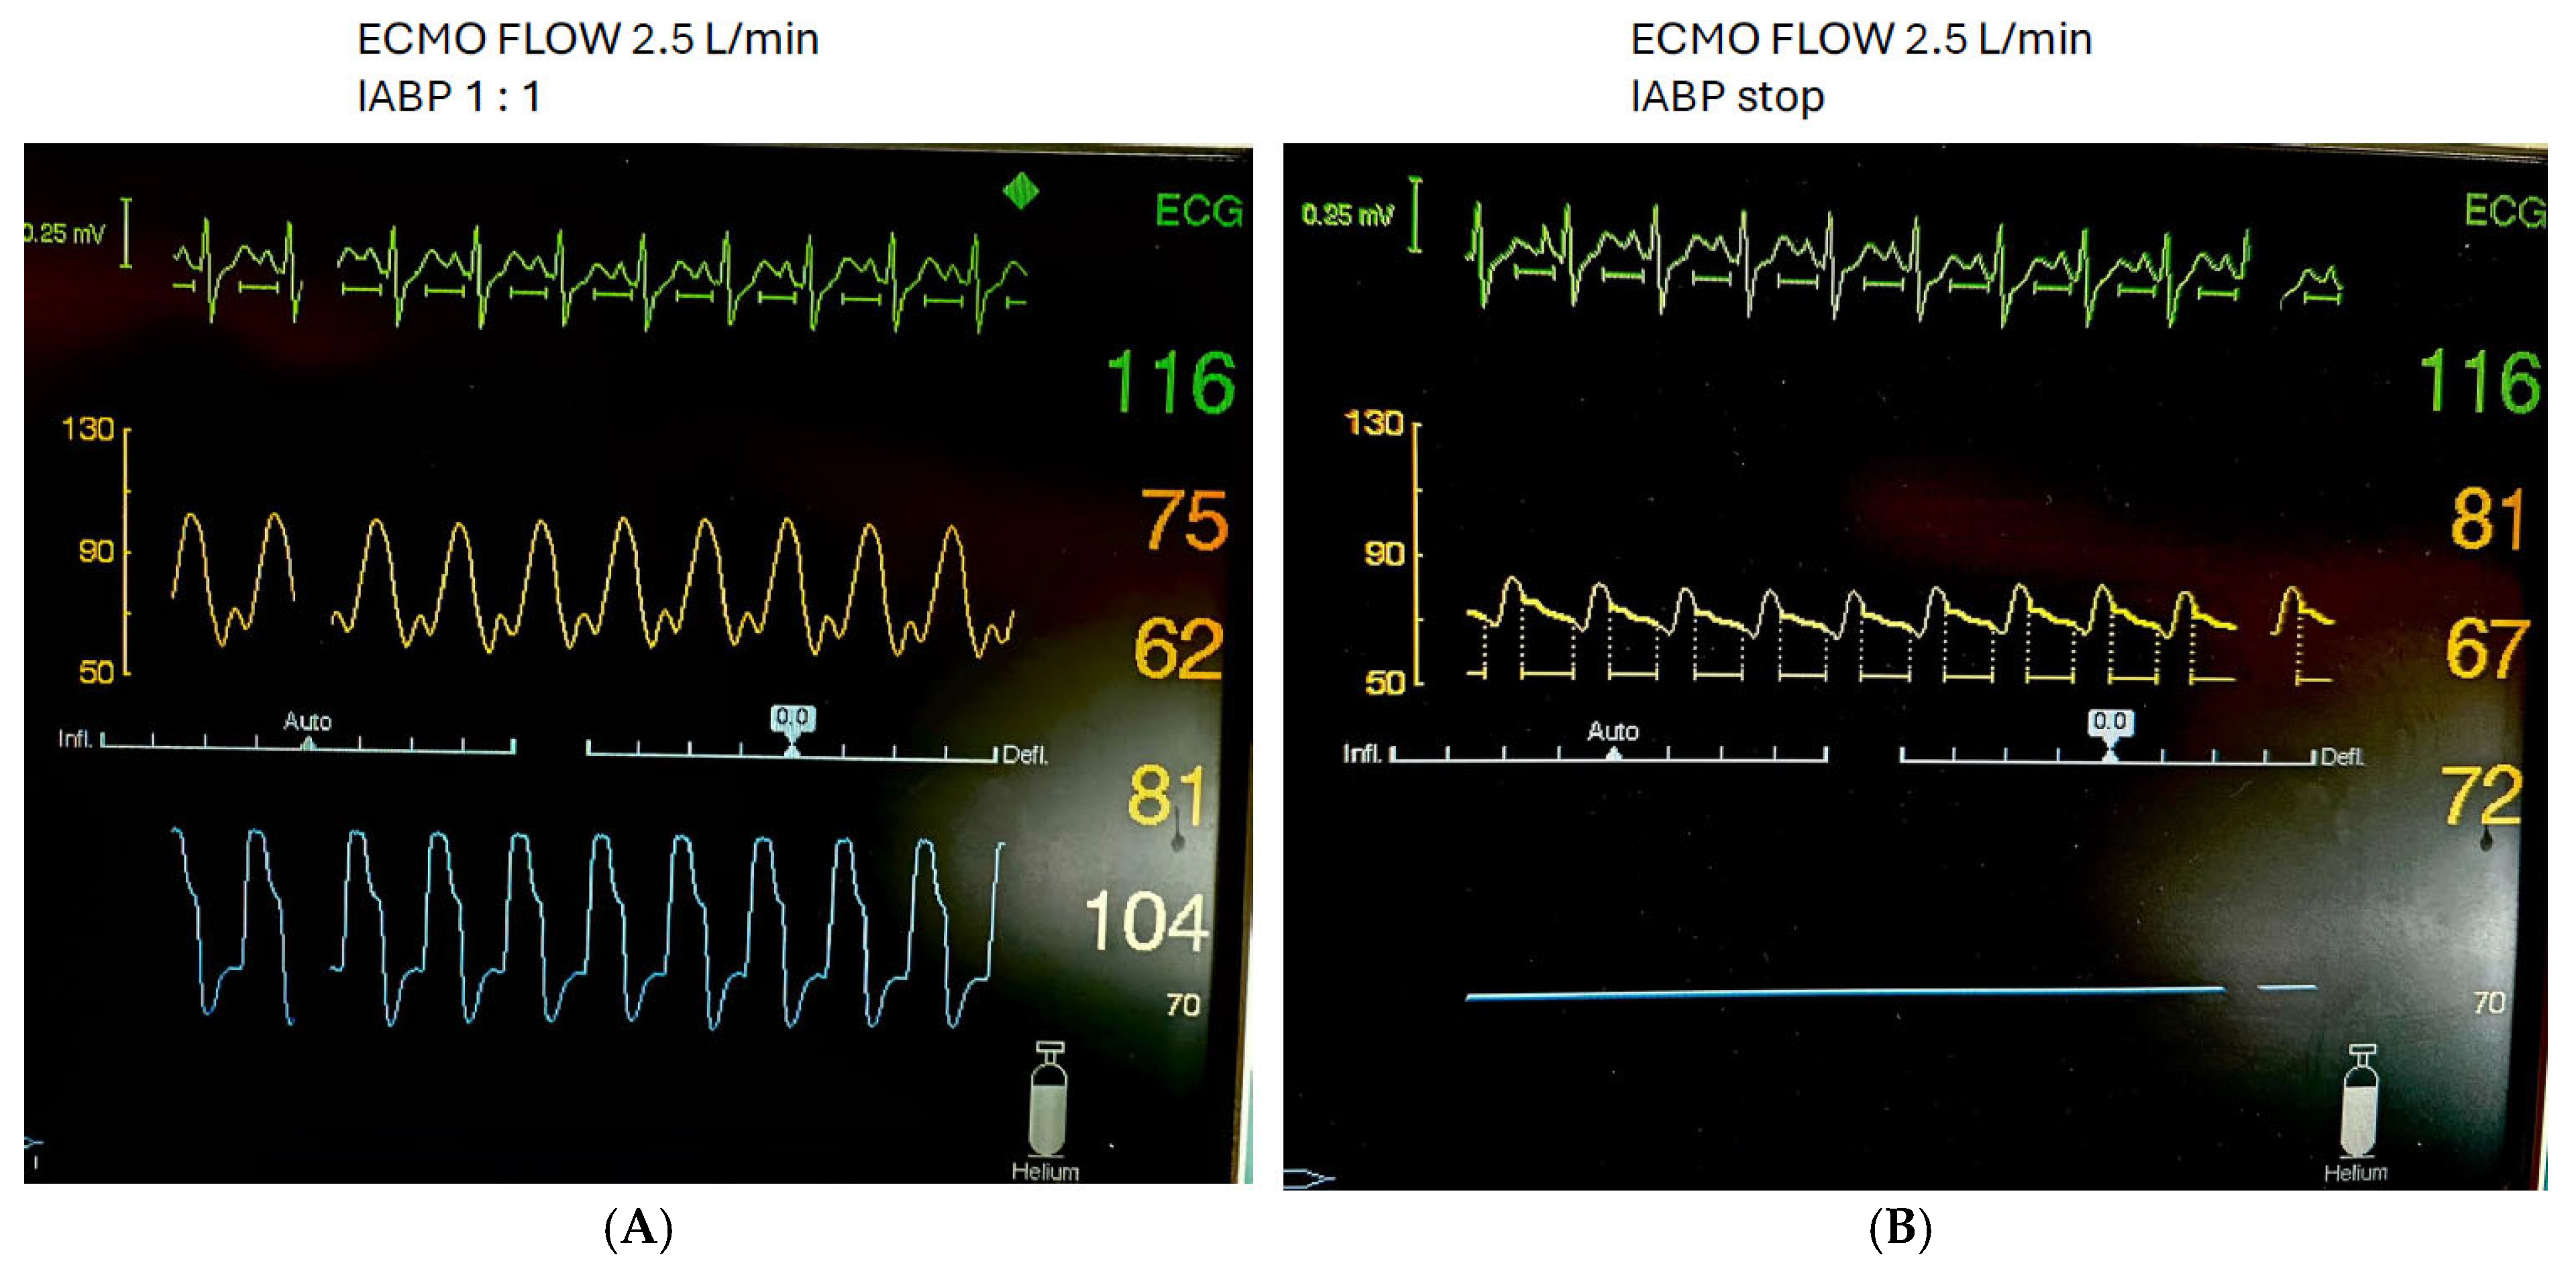

Patients were in a supine position, sedated, intubated on mechanical ventilation, and on VA ECMO (Cardiohelp, Maquet Getinge, Rastatt, Germany) with concomitant IABP (Cardiosave IABP, Maquet Getinge, Rastatt, Germany). We used the largest fiberoptic balloon according to patient height (Figure 1). Patients with inadequate echocardiographic windows and patients hospitalized for less than 24 h were excluded from the study.

Figure 1. X-ray of a patient showing a proximal IABP balloon marker in aortic knob and an ECMO venous cannula with the tip in the right atrium.